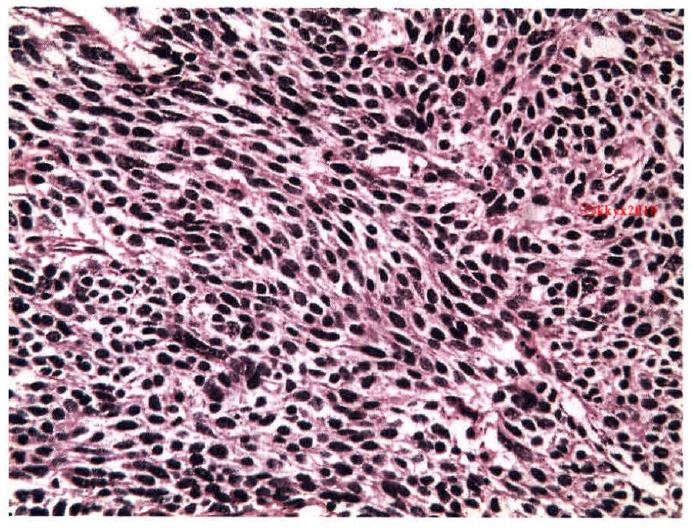

三、从病理上看小细胞肺癌的“坏” 作为肿瘤诊断的金标准,是何如区分小细胞肺癌与非小细胞肺癌的。一般而言,对于预后比较好的肿瘤,大多都能有一定的形态,长得比较像样;但对于那些比较坏的,预后差的肿瘤,很多是不像样堆积,细胞形态上也长得比较奇怪。

小细胞肺癌:癌细胞小,梭形,胞质少,似裸核,平行排列呈片状,一看就不是什么好东西